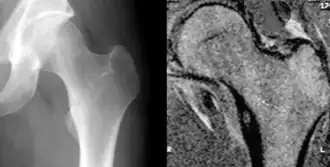

Les radiographies de l'ostéome ostéoïde montrent généralement une clarté ronde, contenant un nidus central sclérotique dense (la lésion caractéristique de ce type de tumeur) entouré d'os sclérotique. Le nidus est rarement plus grand que 1,5 cm.[réf. nécessaire]

La lésion peut dans la plupart des cas être détectée au scanner, à la scintigraphie osseuse et à l'angiographie.

L'IRM n'ajoute que peu aux résultats.